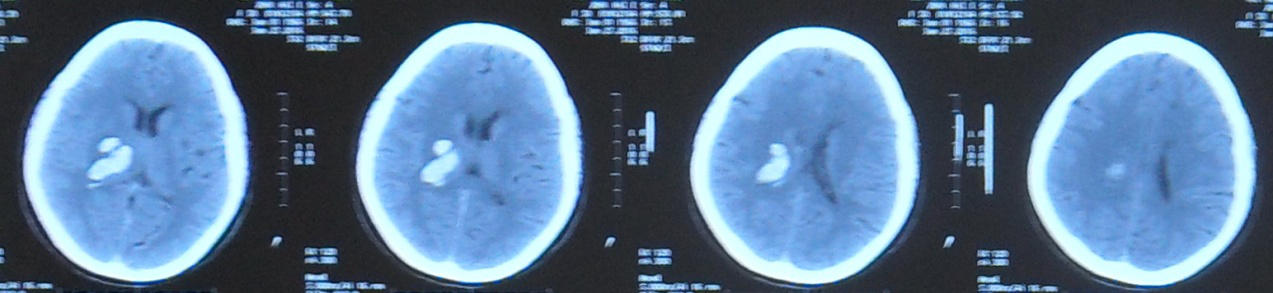

2016年6月25日头部CT片示:右侧丘脑区不规则片状高密度影,周围见水肿带围绕,右侧侧脑室受压变窄,中线结构略向左偏移。

2016年7月08日头部CT片示:与前片比较,颅内出血部分吸收,右侧侧脑室形态部分恢复。

2016年6月25日头部CT片

2016年7月08日头部CT片